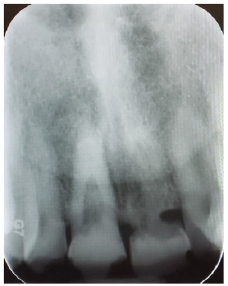

Radiograph and intraoral examinations reveal worn-down teeth [#s 07, 08 and 09] (Figures 1-5) as well as tooth gemination [# 10] (Figures 1-7). The evaluation of periapical radiographs taken of teeth [#s 07, 08, 09, and 10] presents with no evidence of periapical radiolucency. Tooth [# 08], however, shows significant internal root resorption to the mid-way and calcified the apical half of the root to the apex. Tooth [# 09] also shows a significant external/internal root resorption which is more evident on the distal aspect of the tooth, (Figure 7). Both merged segments of geminated tooth [#10] (Figure 6), shows almost completely calcified root canals to the apex. This calcification is also evident in tooth [# 07] (Figure 7).

Figure 7:Teeth #s 08 & 09 radiographic evidence of external / internal root resorptions & partially calcified root canal.

An endodontic consultation was obtained to evaluate the treatment options for teeth [#s 08 and 09]. In addition to the calcified apical half of the root canal of tooth [# 08], a communication between the external and internal root resorption appears more towards the cervical third zone of the root. Tooth [# 09] has external root resorption with an extended resorbed canal. It was stated that root canal treatment is not indicated for either tooth and they should be monitored and planned for the extraction.